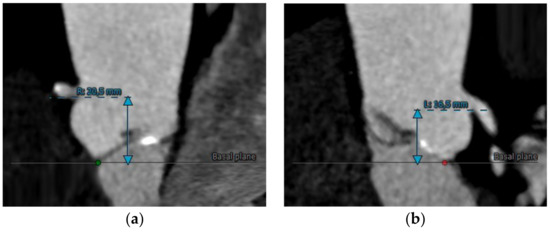

MDCT is crucial to identify the distance from the annulus/leaflet hinge point to the left main and right coronary ostia and the length of the corresponding coronary cusp (Figure 6a,b). Multiplanar, three-dimensional techniques allow better visualization and assessment of these complex structures and their relationships. For this reason, CT represents the preprocedural imaging gold standard for the evaluation of the risk of coronary occlusion. Even if there is no threshold value contraindicating the procedure, an increased risk of coronary occlusion was reported in patients with a coronary ostial height from the annulus < 12 mm and a sinus of Valsalva mean diameter < 30 mm. To ensure reproducibility, the height of the coronary ostia perpendicular to the plane of the annulus should be measured with an electronic caliper from the plane of the ring to the bottom of the ostium. No recommendations exist as to whether these measurements should be performed in systole or diastole [24].

(a) Right and (b) left coronary ostia height assessment by CT images.

Ribeiro et al. found that coronary occlusion most commonly affects the left coronary (88.6 per cent) and occurs more commonly in women and following balloon expandable TAVI. In a systematic review, several parameters were found to be possible predictors of procedural complications: a low-lying coronary ostium < 10 to 12 mm from the basal leaflet insertion to the coronary ostium as measured by MDCT, mean sinus of Valsalva diameter of <30 mm, and sinus of Valsalva diameter/annular diameter ratio of <1.25. Furthermore, according to this analysis, women appear to be more subjected to coronary occlusion because of smaller aortic root dimensions and lower coronary ostial height [52]. Probably, significantly oversized THV or aortic root dissection, the displacement of native bulky aortic leaflets, impingement of the coronary ostia by the THV support structure, the embolization of calcium, thrombus, etc., are the mechanisms underlying coronary obstruction.